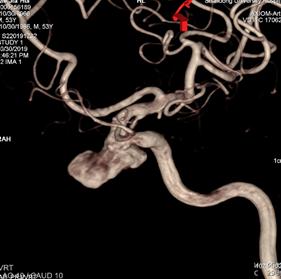

术前造影:

左侧颈内动脉C3段大动脉瘤,大小约23*11mm,瘤颈长度7.4mm,载瘤动脉远端直径约3.8mm,近端直径约4.2mm。

重新行3D造影,根据目标动脉瘤及载瘤动脉选择角度,路图下在0.014 Synchro2微导丝引导下将WILLIS®覆膜支架(4.5*16mm)准确定位至左侧颈内动脉C3动脉瘤位置。

3D重建图示支架贴壁良好。